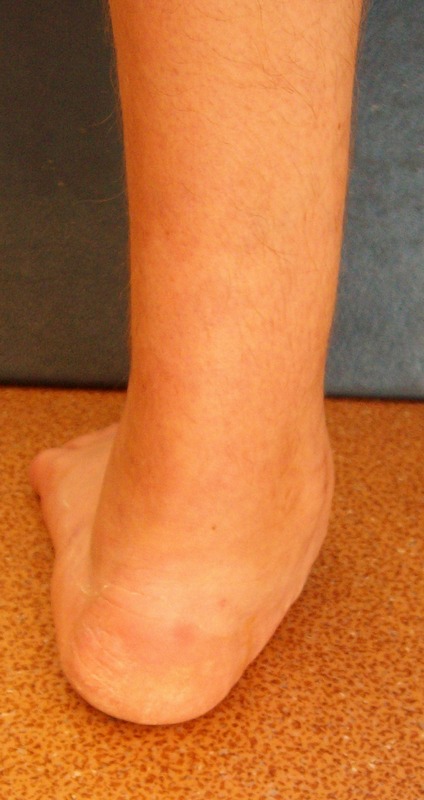

При осмотре имеется плоско-вальгусная деформация левой стопы, болезненность в пяточной области в проекции винта, тугоподвижность в области шопарова сустава. На тыльной поверхности рубцы. План лечений: удаление винта с подошвенной области, корригирующий реартродез в щопаровом суставе. Как удалить остатки винта? Возможно, понадобится реартродез голеностопного или подтаранного сустава.

Now patient complains to deformation and instability in left stop, a pain in the area of ankle joint and in the field of a heel (a projection of the screw).

At survey there is valgus and planus a deformation of left foot, morbidity in calcaneal area in a projection of the screw,the motion in the midfoot. There is the hems on a back surface of foot.